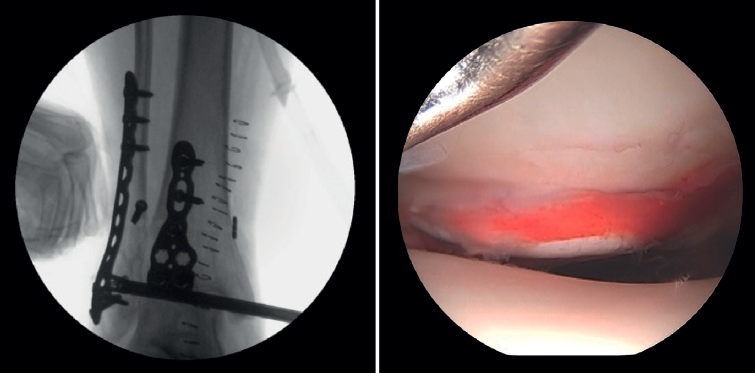

- Diagnóstico de inestabilidad sindesmal: la artroscopia permite la evaluación de la integridad de la sindesmosis y del ECM sobre la radiografía y la TC, sobre todo en la clasificación de las fracturas SER II y IV. Se ha demostrado que la evaluación radiográfica no siempre predice la lesión sindesmal. Además, la artroscopia permite asegurar una reducción anatómica de esta. Takao encontró que el 87% (33/38) de los tobillos con fractura tenían lesiones de la sindesmosis detectadas por artroscopia(20).

La artroscopia permite la visión directa de la sindesmosis y, además, permite su evaluación dinámica(22,21).

- Nos permite diferenciar entre fracturas SER II (en las que no debería existir lesión sindesmal) y fracturas SER IV, en las que sí hay afectación de la sindesmosis, pudiendo estabilizarla(5,23).

- Puede evitar la falsa impresión de un espacio articular medial ensanchado en la fluoroscopia debido a anomalías congénitas.

- Poder visualizar la incisura maleolar junto con el control radioscópico nos permite asegurar un correcto posicionamiento del peroné en la incisura fibularis, sobre todo en las lesiones inestables en las que existe riesgo de mala reducción por acortamiento o rotación del peronéa(5,24).

- Evitar la hipercorrección de la sindesmosis, que es muy artrogénica(5,24) (Figura 6).

Figura 6. A: lesión de sindesmosis; B: control de la reducción para evitar la sobrecorrección; C: control intraoperatorio de la correcta reducción del peroné en la incisura.